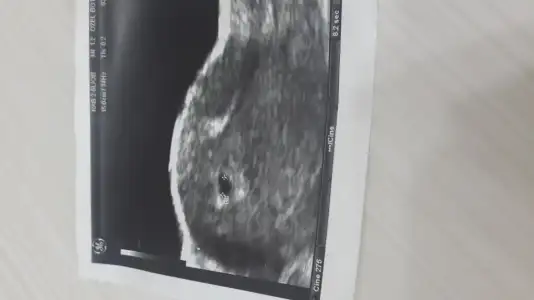

Dün babanemle konuşuyorduk da 5 çocuk hem de 2'şer yaş ara ile (yani 1 yıl ara ile hamile kalmış) dünyaya getirmiş. O zamanlar çamaşır makinesi bulaşık makinesi de yok tabi.. Doktora gitmek- ultrason- kalp atışı dinlemek- cinsiyet öğrenmek vs yok

Şimdi kendimizi düşünüyorum da yok kese oluştu, bebek oluştu, kalbi attı, yok beta değerim şu oldu, o oldu bu oldu.. Resmen 9 ay sonunda birer kadın doğum uzmanına dönüşücek kadar bilgi ediniyoruz:) Bi de yediğimiz içtiğimiz hiçbir şey o zamanlar ki gibi doğal değil, cep telefonu bilgisayar internet radyasyon alıyoruz, hava desen oksijen namına bir şey alamıyoruz... Ya doktor dinlenme veriyor ben değil çamaşırı elde yıkamak çamaşır makinesinin kapağı zor açılıyor diye onu bile açmıyorum.O zamanlarda babanemde benim yaşadığım hiçbi sıkıntı yokmuş biri elinde biri karnında biri sırtında çamaşır yıkar asarmış ... İşte çok fazla bilgi edinebiliyoruz ama çok fazla da risk altındayız.. Allah hayırlısı ile meleklerimizi kucağımıza alabilmemizi nasip etsin inşaAllahhh